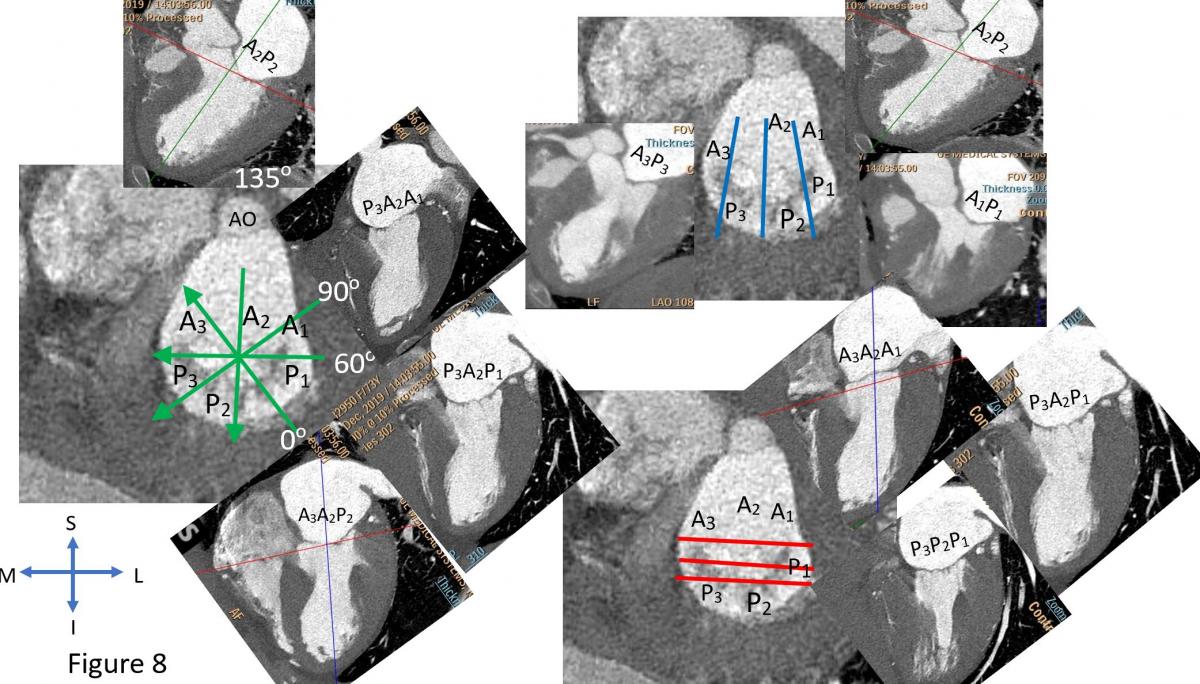

Selection of anatomically and mechanistically suitable patients for MitraClip will largely determine procedural success and short-term outcomes. Currently anatomy and mechanism of mitral regurgitation is primarily evaluated by detailed TEE assessment of mitral valve (Figures 6-7). Cardiac CT (Figure 8) can be used when there is requirement for better assess leaflet calcification if TEE is uncertain. It is important to have standard imaging protocol and terminology for communication between TEE imager and implanter prior, during and post clip for procedural efficiency, procedural success and outcome of the intervention.

Figure 8: Mitral leaflet segmentation is illustrated in cardiac CT views which is equivalent to corresponding TEE views which can be useful in orientation and in case of leaflet calcification for preprocedural planning. CT can also provide views for fluoroscopic view of projection of each segment of mitral leaflets.

To facilitate the communication, both echocardiographer and implanter should be familiar with essential TEE imaging views during mitral clips (Figures 6-8). For transseptal guidance, bicaval TEE view and short-axis basal heart (aortic valve) view are commonly used and often in a XPlane/biplane view (Figure 9). For device advancement guidance in the LA to mitral valve oblique 45 degree view of left pulmonary vein, left atrial appendage/coumardin ridge is often used (Figure 9). For mitral valve, 4-chamber (Figure 7), commissure 2-chamber view (Figures 7-8), LVOT long-axis or 3-chamber view (Figures 7-8) are most commonly used. Off axis 2-chamber views (Figures 7-8) and off-axis LVOT views (Figures 7-8) are used to see P1/A1 and P3/A3 segments of mitral valve. 3D TEE of en face mitral valve view with and without color Doppler flow mapping (Figure 10) is used to guide positioning clip system and clip arm alignment.